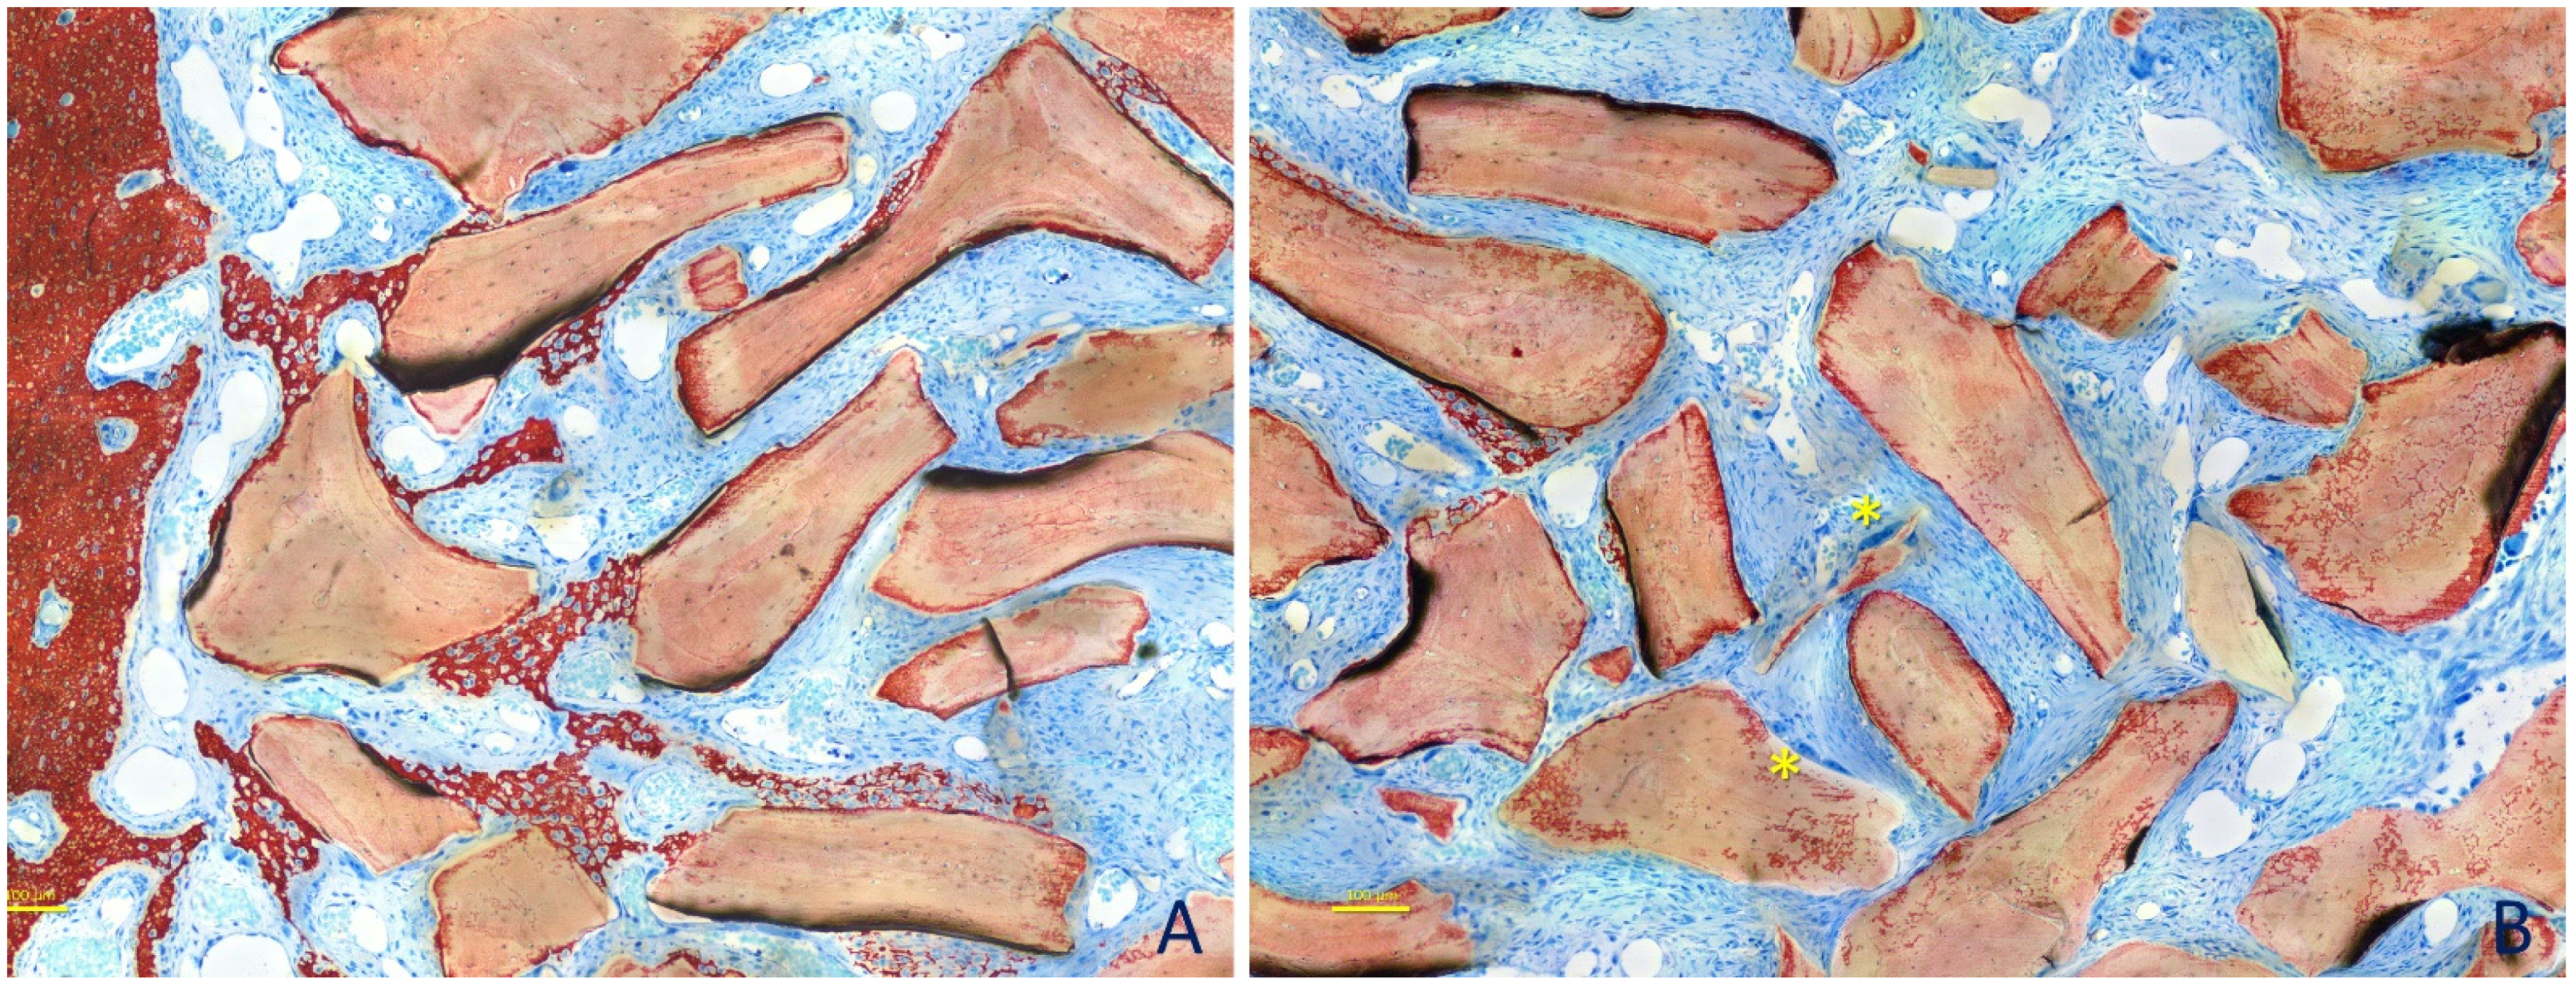

2.3. Surgical Procedures

2.5. MicroCT Evaluations

3. Results